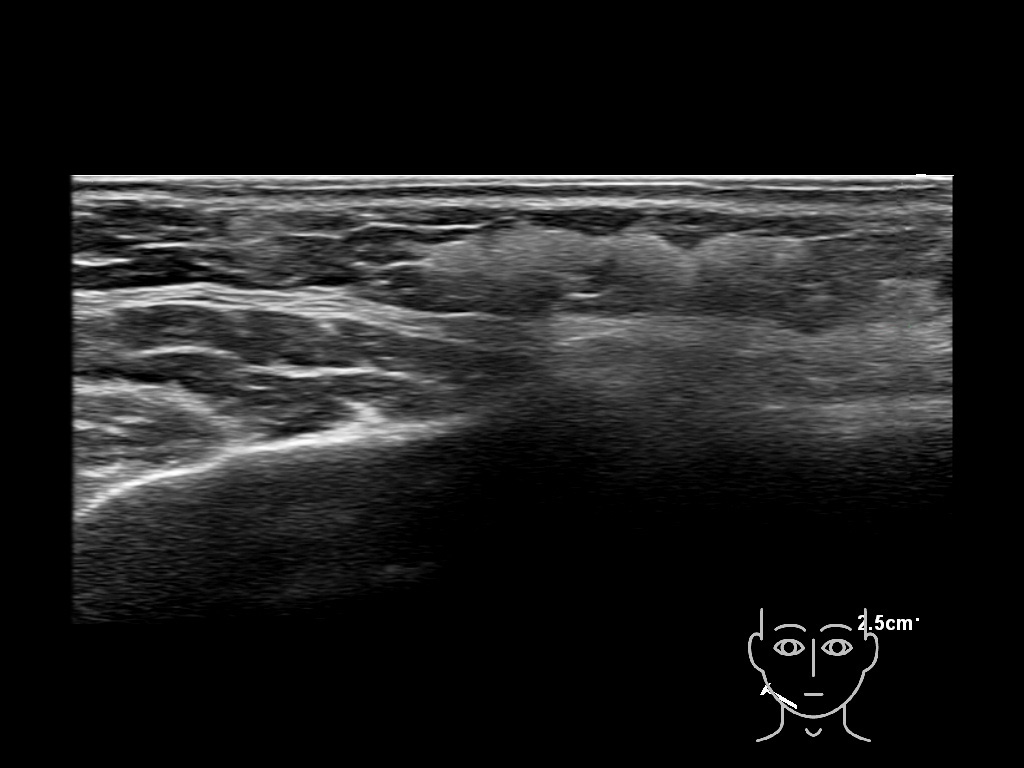

Draw in the image on the right where the fillers are located. To check if your answer is correct, please click on the secondary image.